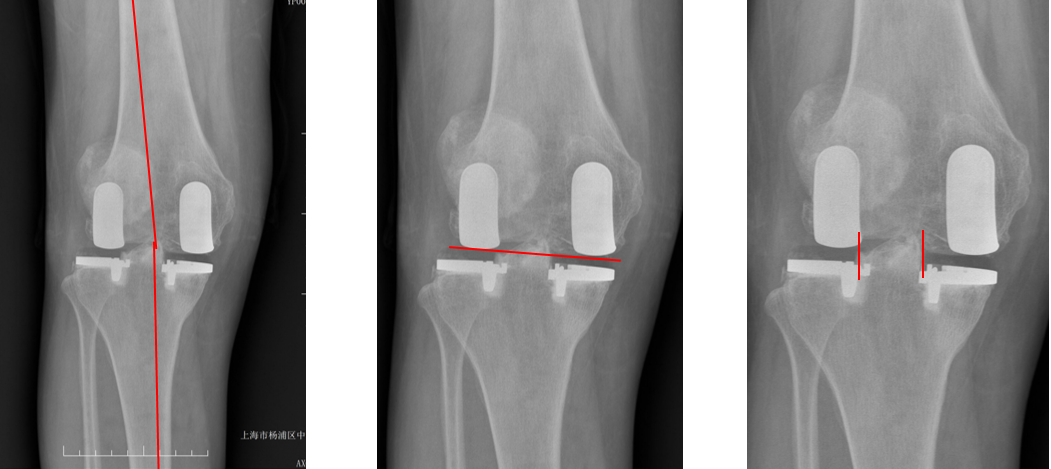

假体位置分析

正位片标准胫骨和股骨假体位置

AP位假体位置:胫骨假体轻度外翻,外侧缘与胫骨平台外侧缘齐平; 股骨假体长轴与胫骨假体垂直,与胫骨假体中线一致。

侧位片标准胫骨和股骨假体位置

侧位片假体位置:股骨假体后倾38°,假体后缘与股骨后髁齐平,胫骨假体后倾3°,与胫骨平台前后缘齐平。

标准胫骨和股骨假体位置

胫骨假体厚度合适

胫骨垫片厚度合适:术前外翻畸形基本矫正,残留2-3°外翻

胫骨假体后倾角度大

侧位片胫骨假体位置:胫骨假体后倾15°,前后缘齐平。

股骨假体偏小

侧位片股骨假体位置:股骨假体偏小,与胫骨假体后缘不齐平;屈曲35°,未包容股骨后髁。

股骨假体偏内放置

AP位胫骨与股骨假体位置:股骨假体中轴线与胫骨假体中线不一致,偏内侧,且外翻。

股骨假体偏外放置

AP位胫骨与股骨假体位置:股骨假体中轴线与胫骨假体中线不一致,偏外侧,且内翻

矫正不足、矫枉过正